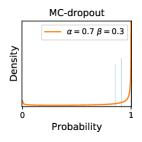

5.1 Distribution of Uncertainty Scores

Distribution of Uncertainty Scores Across Different Severity Levels As explained in Section 3, each uncertainty metric essentially defines an order/ranking among the data points. We conducted an analysis to better understand what data will be assigned high uncertainty under a particular uncertainty metric . Picking out the highest ranked data points (), we calculated the ratio of data points from each SL. Figure 4 summarizes the results as box plots for the Kaggle-DR and the Messidor-2 datasets; additional detailed statistics can be found in Table S.1 in the supplementary materials. From the plot and table, SL1 & SL2 examples account for a higher proportion among the top-ranked uncertain examples across the three ensemble methods. This finding matches our intuition that incipient disease examples (SL1 & SL2) are more likely to be considered uncertain by ensemble methods due to their ambiguity.

Comparing the three ensemble methods in Figure 4, the stacking ensemble method has the highest ratios of SL1 & SL2 data among the high-uncertainty examples it identified under both mean and var. TTA showed slightly better performance than MC-dropout but still falls behind the stacking ensemble method. Considering the fact that SL0 examples accounted for the majority of the dataset, the stacking ensemble method was much more precise (specific) in selecting truly ambiguous data points that were difficult to classify. From Figure 3, we can also see that the stacking ensemble method greatly outperformed the other two methods in finding false negatives under both mean and var uncertainty metrics.

In contrast, the MC-dropout method showed the worst overall performance among the three, as it can be seen from the high ratios of SL0 examples among the uncertain negatives in Figure 4. The histograms in Figure 2 provides another perspective to look into the phenomenon, where a decent proportion of MC-dropout model’s predictions on SL0 inputs entailed low confidence (far from 0 or 1), which from another angle explained why MC-dropout was less specific in terms of lower FNP; many no-DR inputs (i.e. SL0) were erroneously assigned high uncertainty by MC-dropout models.

It is still an open question why the evaluated MC-dropout networks signaled relatively high uncertainty on SL0 & SL3 & SL4 data that are less likely to be ambiguous. We conjecture that much of the “uncertainty” indicated by disagreement among test-time dropout samples actually reflects the stochastic nature of dropout networks rather than the real decision uncertainty associated with the data. It is worth noting that the MC-dropout model we evaluated was not weak per se; they all achieved above Area Under Curve (AUC) scores on test sets. The weakness of individual test-time samples (which explains their low-confidence predictions on SL0 & SL3 & SL4) might have been hidden when they are aggregated into an ensemble—a well-known advantage of ensemble learning. Our results suggested that the uncertainty information given by implicit ensemble methods such as MC-dropout and TTA might not be as reliable as that from explicit ensemble approaches (e.g., stacking ensembles). Similar findings on MC-dropout can be found in some previous papers [1].

As discussed in Section 5.1 and Section 5.3 in the main paper, the mean metric and the stacking ensemble will have better performance in the precision (specificity) on the ambiguous data. Here, more detailed results are shown in Figures S.3 & S.6 and Table S.1. Figures S.3 & S.4 show the histograms of the uncertainty score for Kaggle-DR and Messidor-2 datasets that are the in-distribution (i.d.) dataset in our experiment and FigureS.5 & S.6 show the histograms for ImageNet and CIFAR-10 datasets, which is the o.o.d. datasets in our experiment. Each group of histograms contains results from the three evaluated ensemble methods (stacking ensemble, MC-dropout and TTA) and the three uncertainty metrics (mean, var and kl). Additional detailed results not displayed in Figure 4 can be found in Table S.1, which shows the proportion of the data of different SLs varies across different . For comparison, we also included in Table S.1 the results from single learners, and the proportions of data of different SLs (before any selection was made).